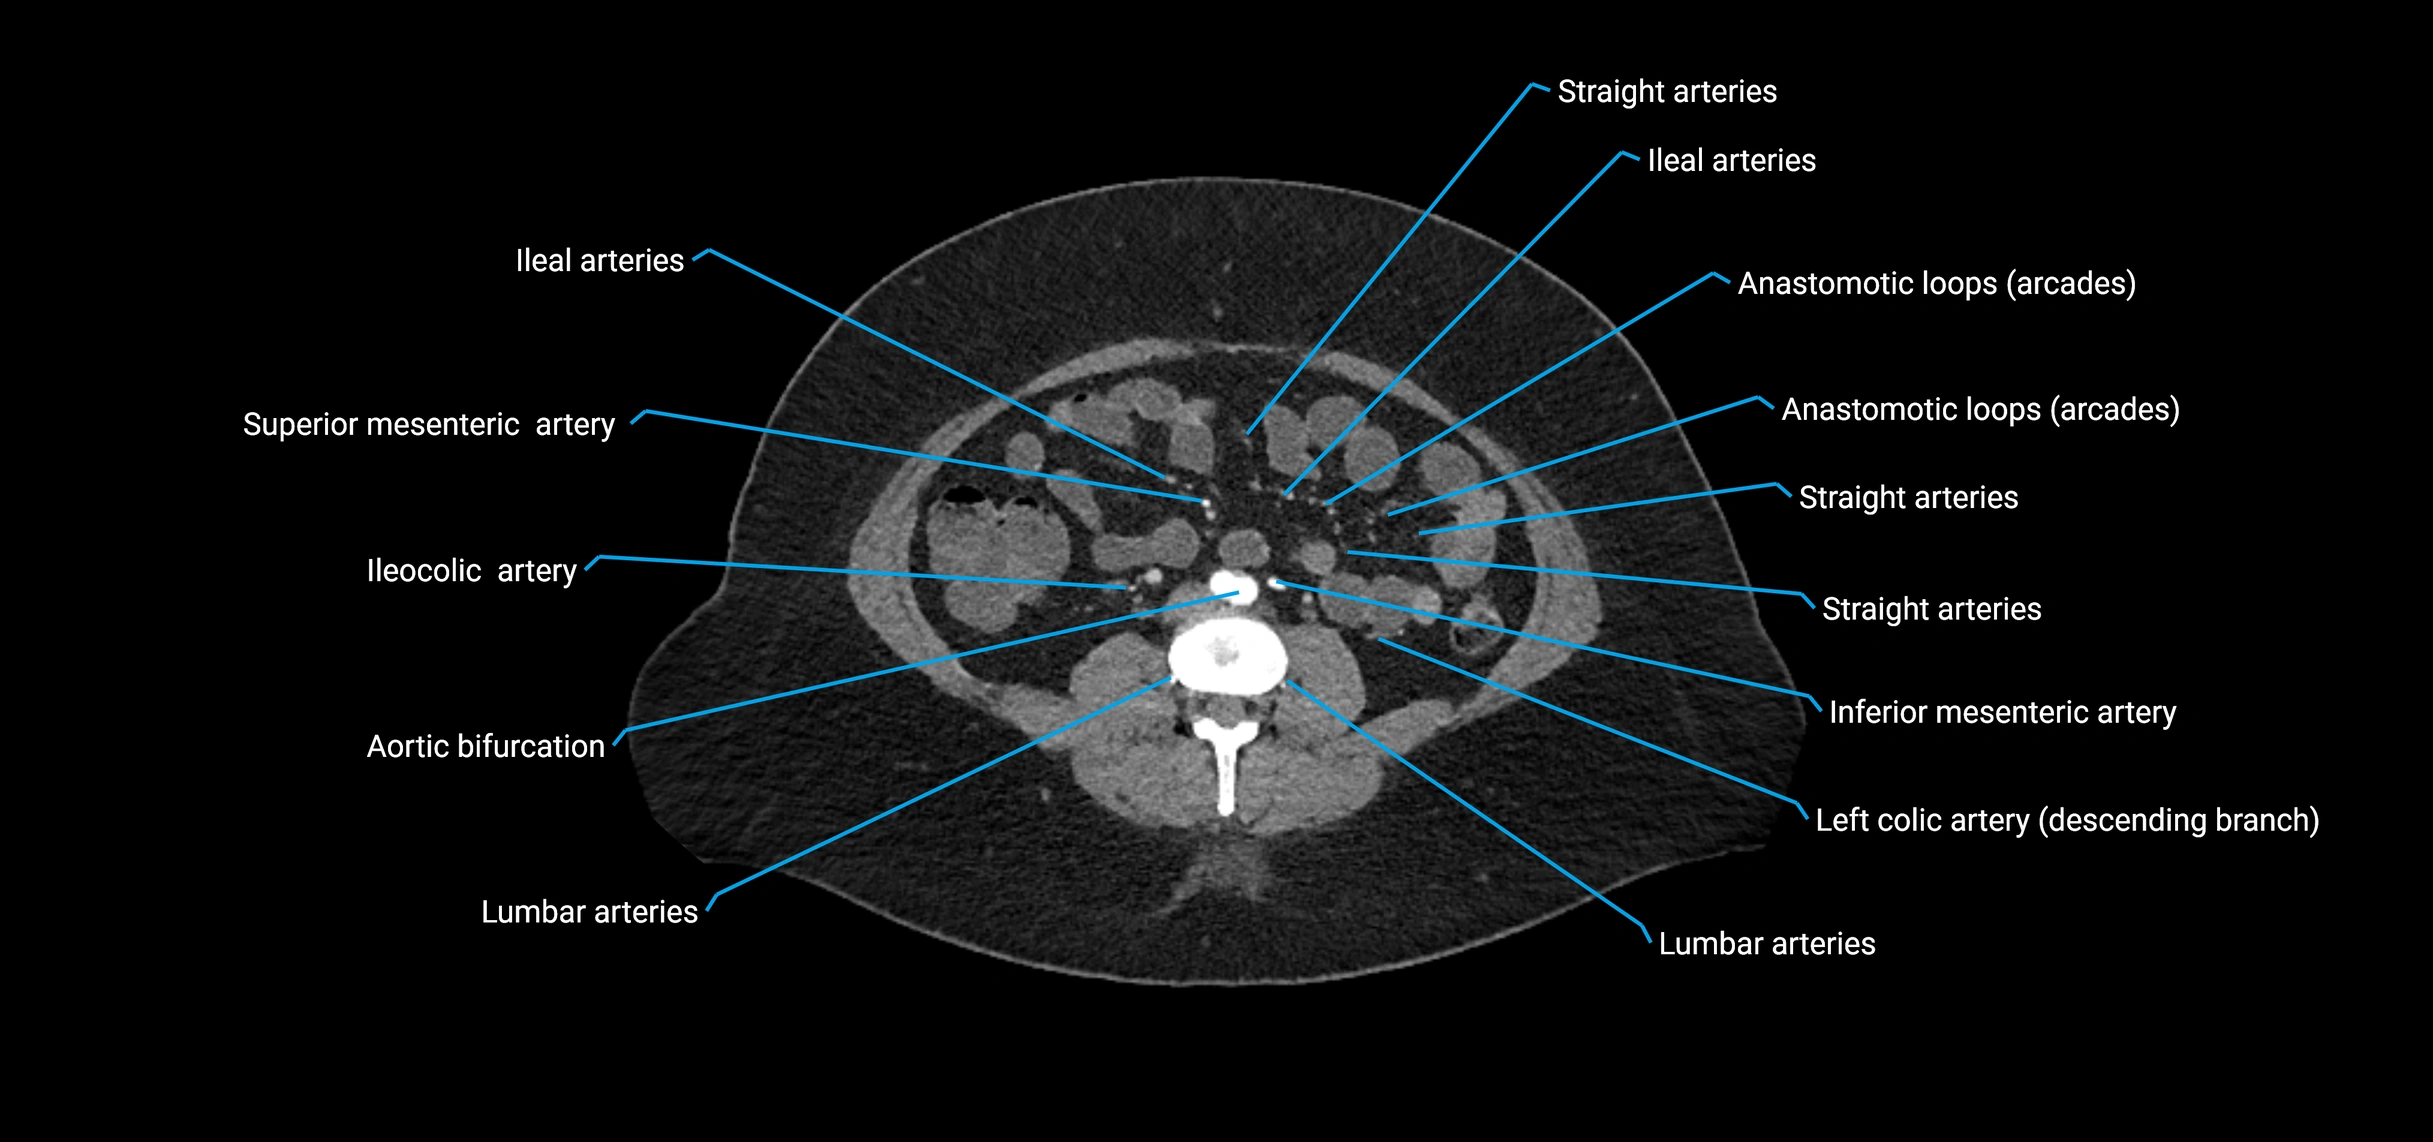

Contrast-enhanced CT (CTA):

• Gold standard for abdominal aortic imaging

• Provides excellent detail of lumen, wall, aneurysm, thrombus, and branch vessels

• Multiplanar and 3D reconstructions help in aneurysm measurement, stent graft planning, and dissection evaluation

• Detects acute rupture, traumatic injury, or occlusion with high sensitivity